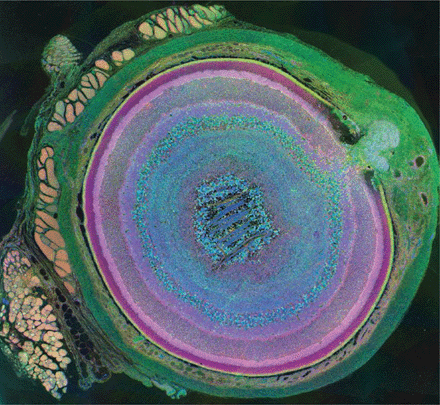

La forma più facile da capire è senz’altro la fotografia, anche se in questo capo le foto diventano delle vere composizioni artistiche. Il primo premio, infatti, è stato aggiudicato da uno scienziato di neurologia dell’università di Salt Lake City. La sua opera è consistita nell’affettare il bulbo oculare di un topo in 120 fettine più sottili di un nanometro. Ha poi evidenziato con diversi colori i vari componenti dell’occhio tramite anticorpi specifici, permettendo così di capire a cosa serve ogni zona del bulbo oculare: cellule muscolare, tessuto sclerale, e via dicendo. Vediamo qui sotto il risultato: